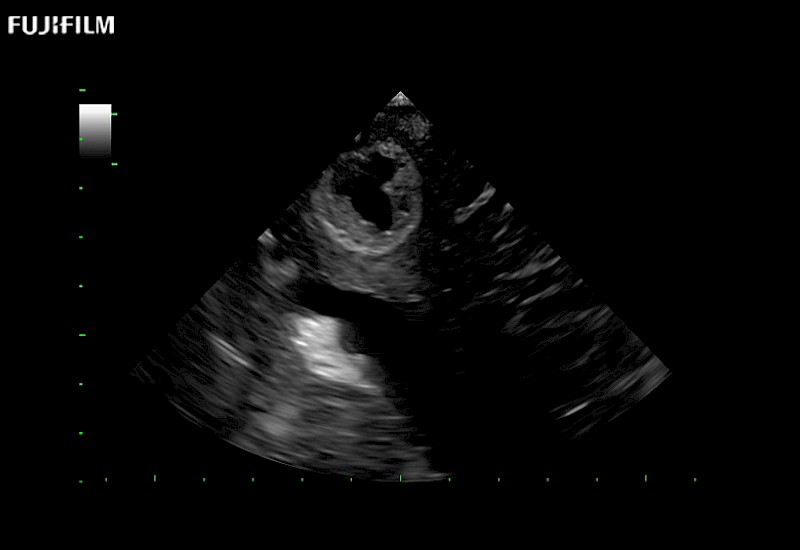

Extraordinary high-resolution digital imaging

Exceptional transducers

for use during: Cranial guidance, Burr-Hole guidance, Spinal Cord guidance, Pituitary guidance, Micro-Surgery guidance

Our dedication to neurosurgery allows us to offer superior image quality, outstanding system reliability and intuitive use of cutting edge technology.